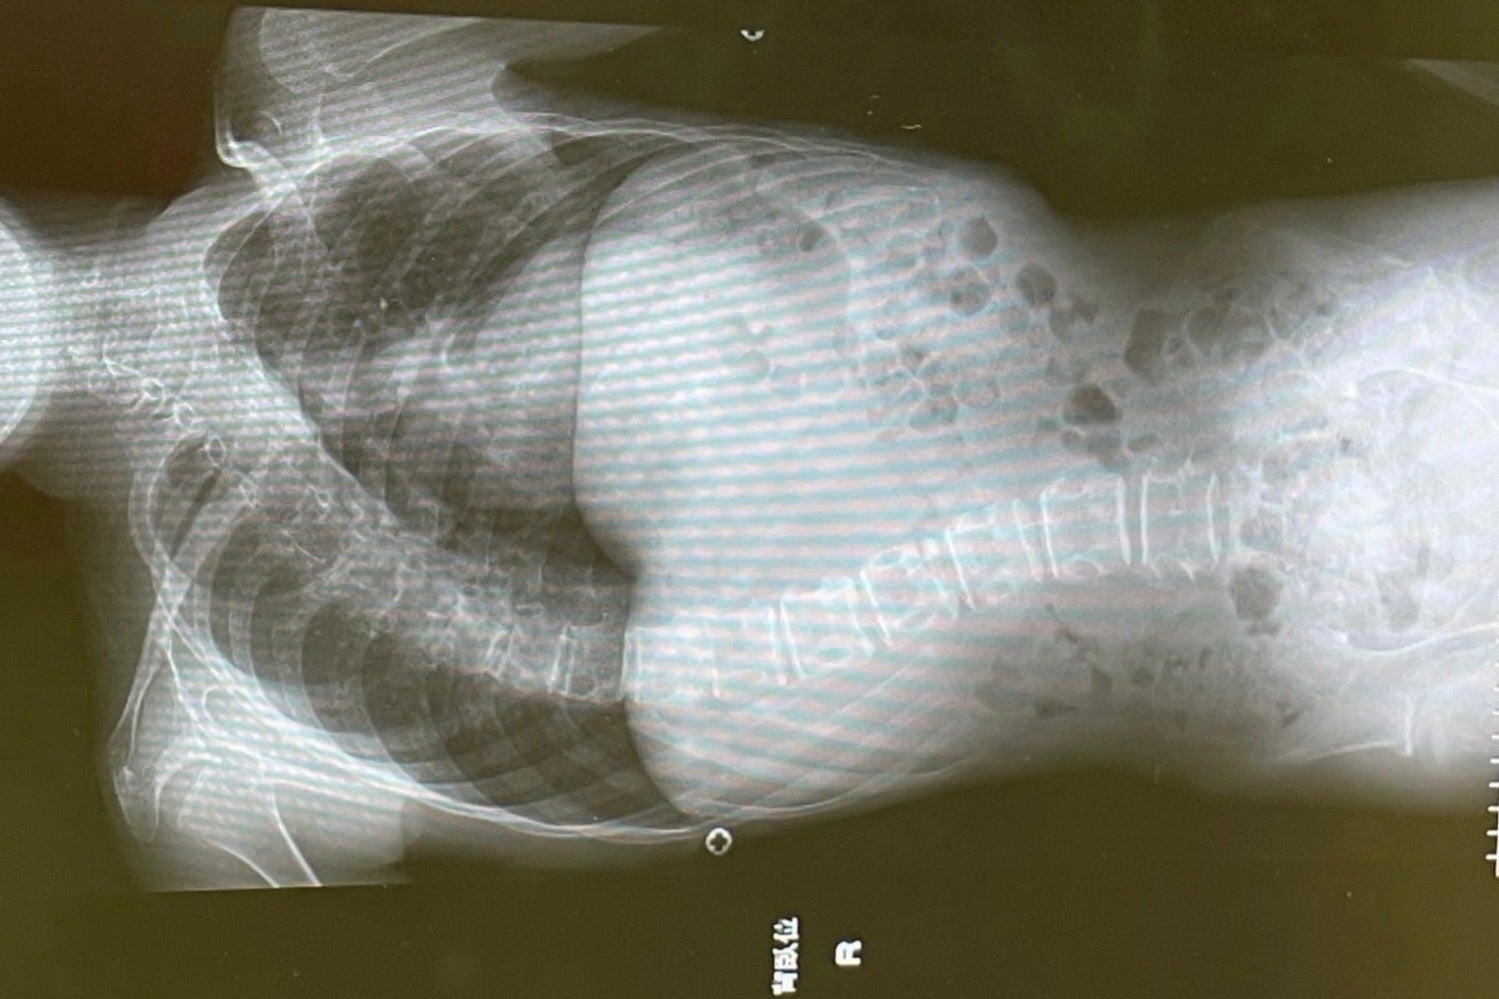

整体の機械「リスカル」を開発し2021年から販売しています。頭痛・肩こり・腰痛・膝等に施術可能ですが、その機械を使って「小児脳性麻痺」など「障がい」のある子供、又は「側湾症」「関節の変形」に効果的かどうか試しています。しかし、1人ではスピードが遅いので、日本小児障がい児支援協会の代表理事、青山かほる先生、や協会の会員の方々に協力して頂き数名で試し症例やエビデンスを集めたいと考えています。

このプロジェクトで実現したい事は、小児脳性麻痺など障がいのある子供さんや親御さんに希望を持って頂く事です。現代の医学や科学では障がいの原因が解明されていません。治療法も外科的手術しかなく、手術したからといって、症状が改善する確率は低いと聞きました。GLITTER式のトレーニングやマッサージとリスカルの相乗効果で症例とエビデンスを集め、可能性を追求したいのです。

リスカルは腰痛や肩こりなどに施術可能なのですが、脳性麻痺や障がい児、側湾症には効果があるかと青山先生から尋ねられました。私はそのような子供を施術した事が無かったので、一度、施術させて欲しいとお願いしました。青山先生のGLITTERという施術所に行きました。そこには障がいを持つ様々な子供と保護者が次々に訪れます。

立てない子、歩けない子、喋れない子、足が変形している子、側湾症の子、頭が変形している子、全く何もできずに母親が抱いて来る子、など様々な子供たちが来ます。そこでは、その子供たちをGLITTER式のマッサージ、トレーニング、鍼灸、などを施術しています。私は、先生の許可を得て数人の子供さんにリスカルにて施術させて頂きその日は終わりました。